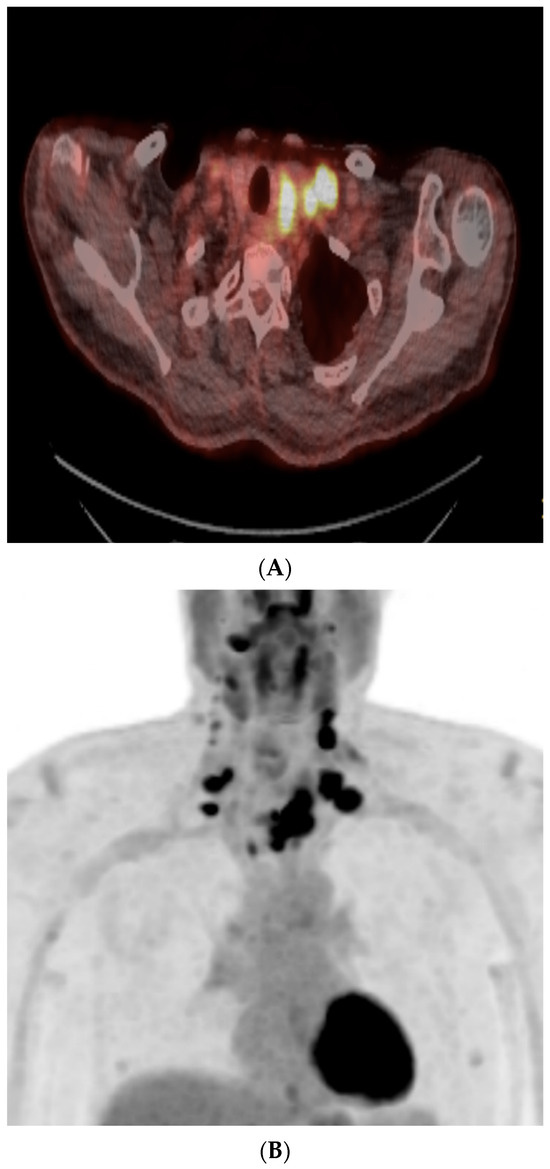

MRI 4 weeks later demonstrated a sustained treatment response. Three weeks later, FDG-Positron Emission Tomography (PET) CT demonstrated uptake in the left lobe of the thyroid gland, bilateral cervical lymph nodes, and superior mediastinal lymph nodes (shown in Figure 5). Subsequent MDM discussion recommended radical thyroidectomy based on data from cohort studies showing improved outcomes [16,17].

Figure 5.

(A,B): Pre-operative PET CT demonstrated uptake within the residual component of the left thyroid mass and the bilateral neck adenopathy but no distant metastatic disease.